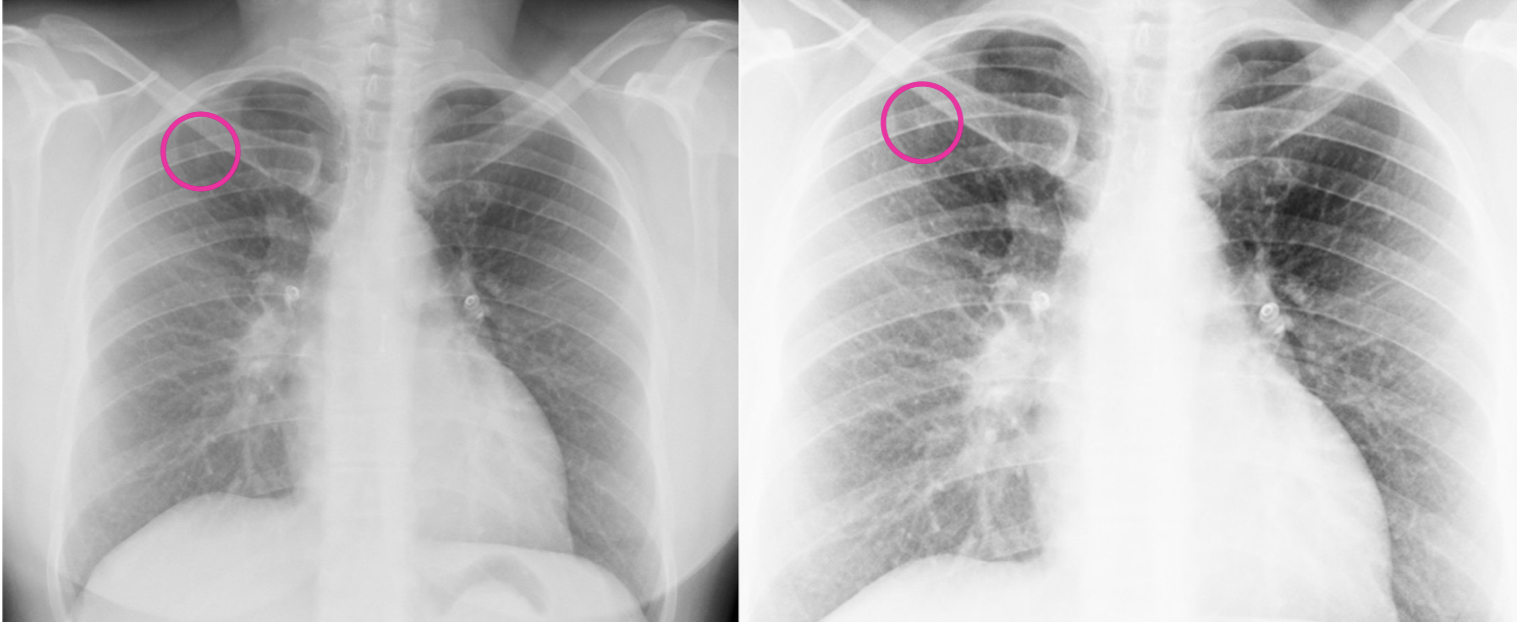

En ella observamos un nódulo radiodenso polilobulado ubicado en el LSD y una gran asimetría de los hilios pulmonares, con engrosamiento del hilio derecho.

TC tórax con contraste. Dado que la radiografía de tórax reveló un patrón sugestivo de neoplasia pulmonar, se decidió hacer un TC como prueba complementaria. EL TC es una prueba con mayor sensibilidad y especificidad para caracterizar lesiones pulmonares. Permite una mejor caracterización del nódulo (tamaño, forma, bordes y densidad), se pueden detectar características sugestivas de malignidad, como bordes espiculados o una tasa de crecimiento rápida.

El TC también facilita la diferenciación entre lesiones benignas y malignas, así como, realizar una evaluación del contexto clínico, es decir, permite buscar otros hallazgos, como adenopatías mediastínicas o lesiones pulmonares adicionales, que pueden sugerir una enfermedad metastásica o infecciosa. En el TC se evidenciaron tres nódulos pulmonares polilobulados, presentes en ambos pulmones. Además, permitió ver que la asimetría hiliar se debía a la presencia de varias adenopatías hiliares derechas de densidad heterogénea y aspecto necrótico, que estaban infiltrando una rama de la arteria pulmonar.